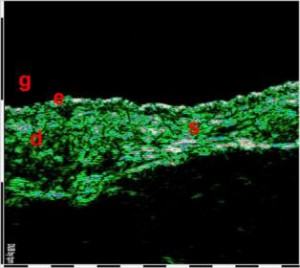

-Υπέρηχος Υψηλής Συχνότητας (HFUS) και Ιστολογία